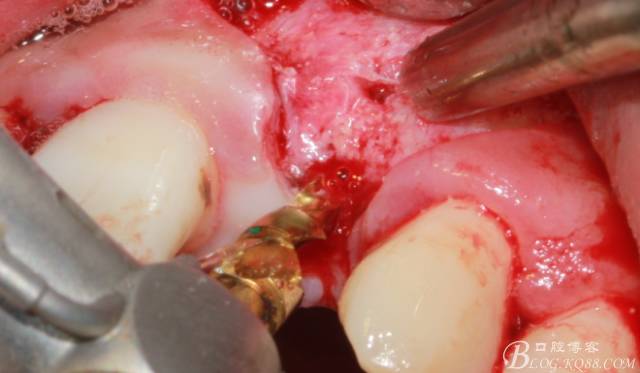

骨擠壓

植入植體